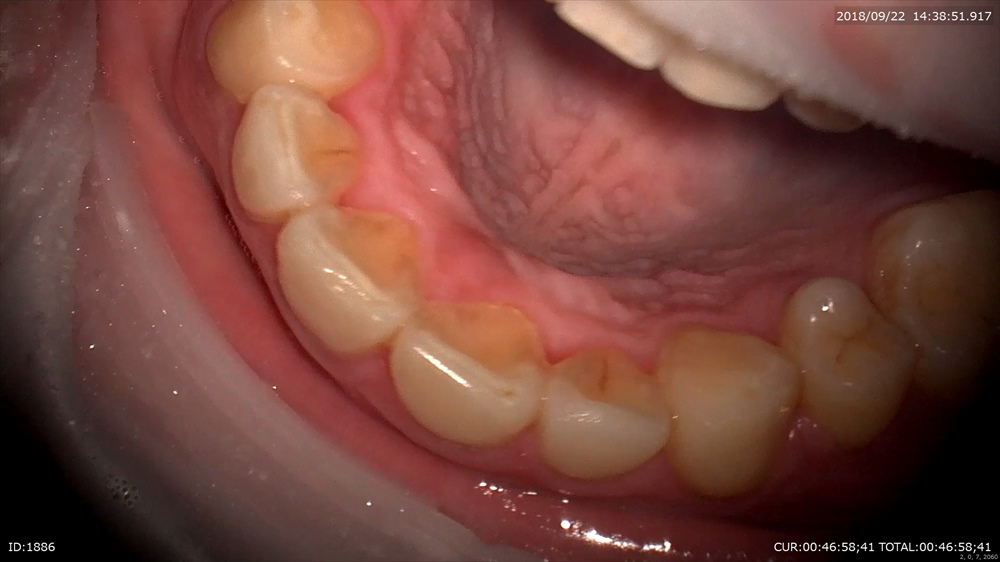

装置除去。ガタガタの歯並びは綺麗になりました。2年かかりました。抜歯症例。

EXTARO300ここまで広範囲に。しかも直視で上顎が見えます。これマイクロを使用している先生がみたら私の言いたい事が解ると思います。

下顎も見える!!

EXTARO300かなり良いです。矯正のブラケットセットにも向いているなー。